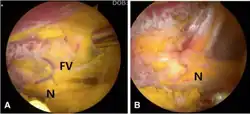

Surgery

Surgery involves a nerve decompression with or without muscle resection.[5] The surgery can be performed with external incisions (open surgery) or endoscopically. Endoscopy allows for complete sciatic nerve visualization and access for decompression in the extrapelvic gluteal space.[1] The goal of surgery is to restore normal nerve kinematics and nerve conduction. During surgery this is measured by nerve conduction studies and electromyography, as well as observing the sciatic nerve mobility while the patients hips are moved.[1][2] This testing can be done before and after the decompression to verify improvement before concluding the surgery.